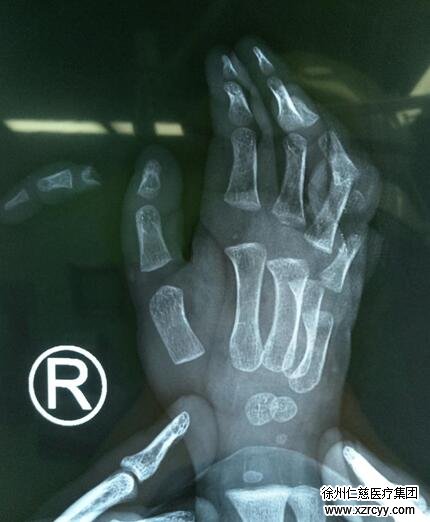

李海建医生接诊后,在急诊清创室内简单查看了下阳阳的伤口,发现阳阳的右手环指近节不全离断、小指近节完全离断,对于仅仅只有2岁的阳阳来说,情况可以说是很严重了。在与阳阳父母充分的沟通后,做完术前检查的阳阳就被送进了手术室。

手术室内,李海建先对阳阳的伤口进行了反复的清创,然后在显微镜下接上了阳阳被绞断的细如发丝的血管、神经、肌腱,手术过程十分顺利。

“给2岁的患儿做断肢、断指再植术,手术和护理难度都较大。”李海建解释,由于小儿的组织非常娇嫩,血管、神经以及肌腱纤细,组织辨认较为困难,血管管径极细,吻合技术要求非常高,很容易出现血管危象,导致手术失败。另外,李海建表示,小儿受伤后因心理承受力、配合情况较差,对疼痛、生活习惯的改变等情况反应较强烈,易哭闹,不配合,给手术及术后护理处置带来极大的负面影响。这其中除了靠医生高超的显微操作技术以及极高的耐心外,还依赖于护士对患儿术后再植手指的精心护理。